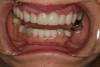

Fig 6. Deep bite, excessive wear, and missing No. 9 present a challenging case for restorative rehabilitation.

Figure 6